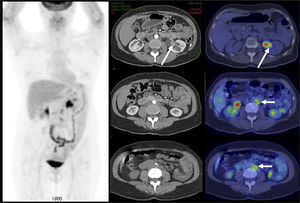

Aunque el PET/CT no figura en el algoritmo habitual de estudio de etapificación, ha ganado terreno rápidamente gracias a ciertos radiotrazadores específicos desarrollados en los últimos años, principalmente aquellos basados en el trazador PSMA (Prostate Specific Membrane Antigen) (22). Varias publicaciones destacan la alta correlación del PET/CT Ga68-PSMA con la RM de próstata al evaluar el tumor primario (23), y su superioridad diagnóstica en etapificación N, al detectar pequeñas adenopatías regionales que pasan inadvertidas con TC o RM (Figura 7) (24). Al estudiar preoperatoriamente a pacientes de riesgo intermedio y alto, Van Leeuwen et al encontraron una sensibilidad de 64% y especificidad de 95% en detección de linfonodos, todos ellos <10 mm, es decir negativos a la TC (25). Ellos sugieren que el PET/CT Ga68-PSMA debiera reemplazar en el futuro a los métodos tradicionales de etapificación N. Los falsos negativos obtenidos corresponden mayormente a ganglios metastásicos <5 mm, los que siguen siendo un desafío diagnóstico para las técnicas de imagen actuales.

La capacidad de las imágenes moleculares de detectar recidiva de manera más precoz que las imágenes morfológicas como la TC, especialmente en áreas con anatomía alterada por la cirugía y/o radioterapia, ha impulsado el uso del PET/CT en estos pacientes. La vasta experiencia en PET/CT utilizando C11 o F18-Colina ha permitido acumular evidencia suficiente para poder incluirlo en las guías clínicas actuales (16). Sin embargo, otros radiotrazadores nuevos como el Ga68-PSMA, que han presentado un desarrollo explosivo gracias a su alto rendimiento diagnóstico, aún mayor que el del PET/CT con Colina, especialmente a niveles bajos de APE, hacen pensar que prontamente las guías clínicas lo incorporarán en sus sugerencias (27) (Figura 8).

En un grupo de pacientes operados que presentaron posteriormente recidiva bioquímica, Morigi et al (26) demostró una significativa mayor sensibilidad del PET/CT Ga68-PSMA comparado al PET/CT F18-Colina para niveles de APE bajos, lo que estaría explicado en parte por la mejor resolución de contraste del Ga68-PSMA, proporcionando una relación lesión/fondo tres veces mayor respecto a F18-Colina. Ellos obtuvieron una sensibilidad de 50% con APE <0.5ng/ml, 69% con APE 0.5-2.0ng/ml y 86% con APE >2.0ng/ml, vs 13%, 31% y 57% para F18-Colina, respectivamente.

Resultados similares exhiben Eiber et al en un análisis de 248 pacientes con alza del APE post prostatectomía radical, con una sensibilidad de 57.9% con APE <0.5ng/ml, 72.7% con APE 0.5-1.0ng/ml, 93.0% con APE 1-2ng/ml, y 96.8% con APE >2.0ng/ml (28).